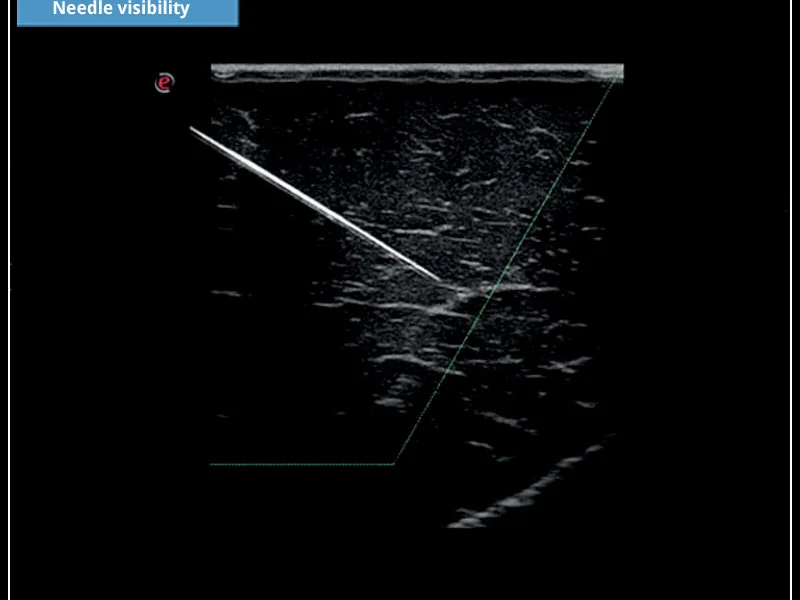

MyLab™X5 - Needle visibility